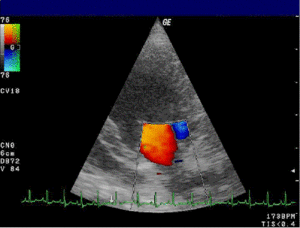

رسم القلب بالصدى

:

تأثير دوبلر

يظهر

قصوراً

في

الصمام المترالي

لكلب

- منظر قمي أيسر.